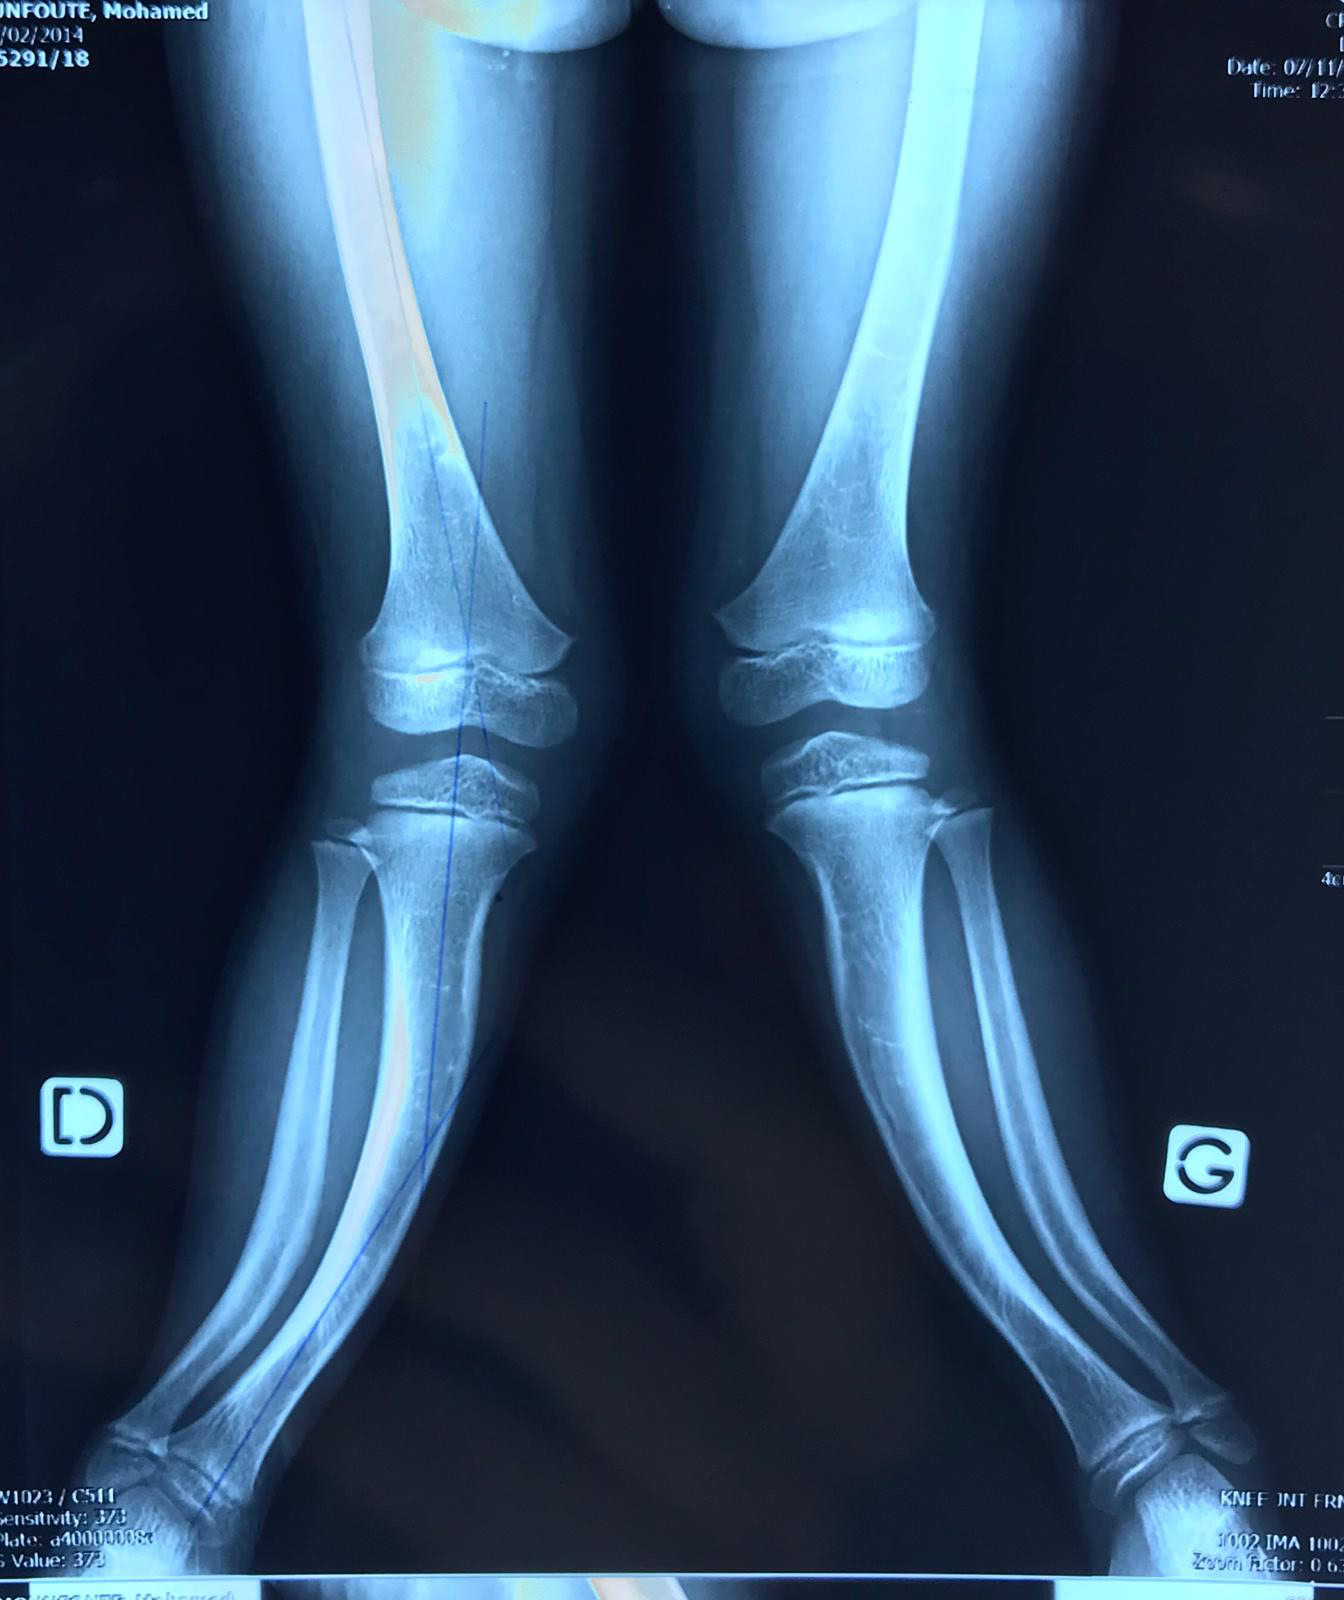

En esta ocasión hemos  tenido más cirugías de perfil pediátrico que en otras ocasiones, desde una amputación de miembro superior a una niña a la que no se pudo salvar su brazo hasta grandes deformidades e infecciones

Las cirugías han sido importantes para poder conseguir realizar todas esas correcciones y la evolución de los pacientes  en el post-operatorio inmediato ha sido satisfactoria.